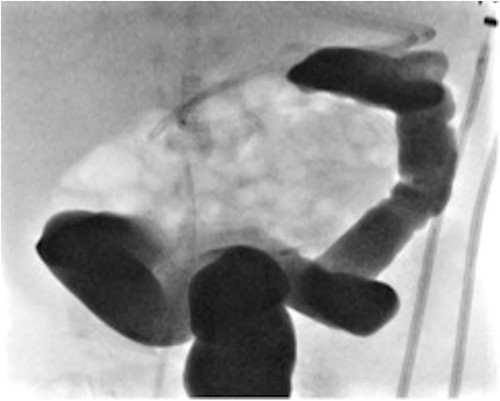

He presented at 6 weeks of age with circulatory shock requiring inotropic support and a short history of sudden abdominal distension and non bilious vomiting. He had been having regular episodes of SVT, all self limiting. Laparotomy demonstrated malrotation and a 540°midgut volvulus with extensive bowel necrosis. A fulcrum of ileum was densely adherent to the descending colon. Following intestinal resection he was left with 40 cm of small bowel from the duodenojejunal flexure, 2 cm of distal ileum and an intact colon. Following recovery from this acute episode he was managed for intestinal failure. A contrast enema was performed 10 days later in advance of stoma closure to examine the area of descending colon to which the ileum had been adherent at laparotomy. This demonstrated failure of passage of contrast proximal to the mid descending colon consistent with acquired colonic atresia (Fig. 1). Due to ongoing high stoma output and inability to progress enteral feeds, the infant proceeded to laparotomy, closure of jejunostomy, resection of colonic atresia, and anastomosis at 3 months of age. Macroscopic evidence of the atresia was encountered (Fig. 2). Histology reported a narrow calibre colon to either side of the atresia with fibrotic submucosa, focal fibrovascular proliferation, and clusters of giant cells. He subsequently achieved enteral autonomy.

Contrast enema showing failure of passage of contrast beyond descending colon.